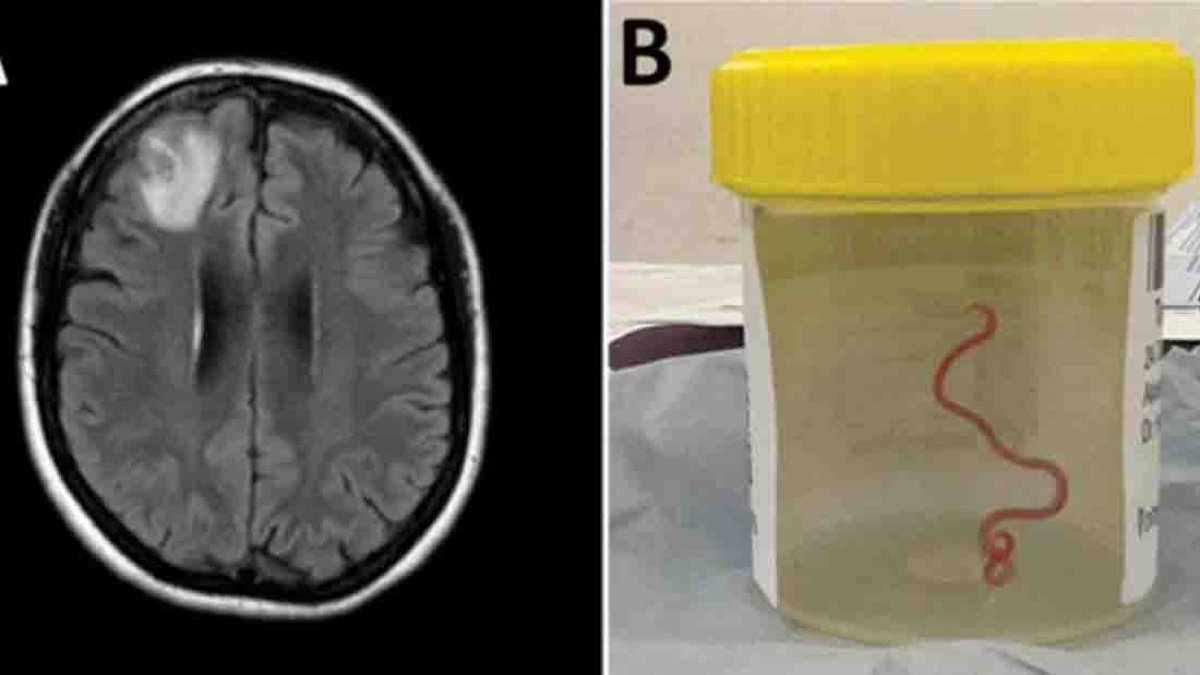

Le extraen del cerebro una lombriz intestinal viva, común en serpientes pitones

AUSTRALIA – Un grupo de neurocirujanos extrajeron del cerebro de una mujer australiana una lombriz intestinal viva de ocho centímetros, el primer caso de este tipo en humanos, según informaron este martes fuentes académicas. El parásito, identificado como Ophidascaris robertsi, es común en las serpientes pitones diamantina, una especie endémica de Australia. “Se trata del…